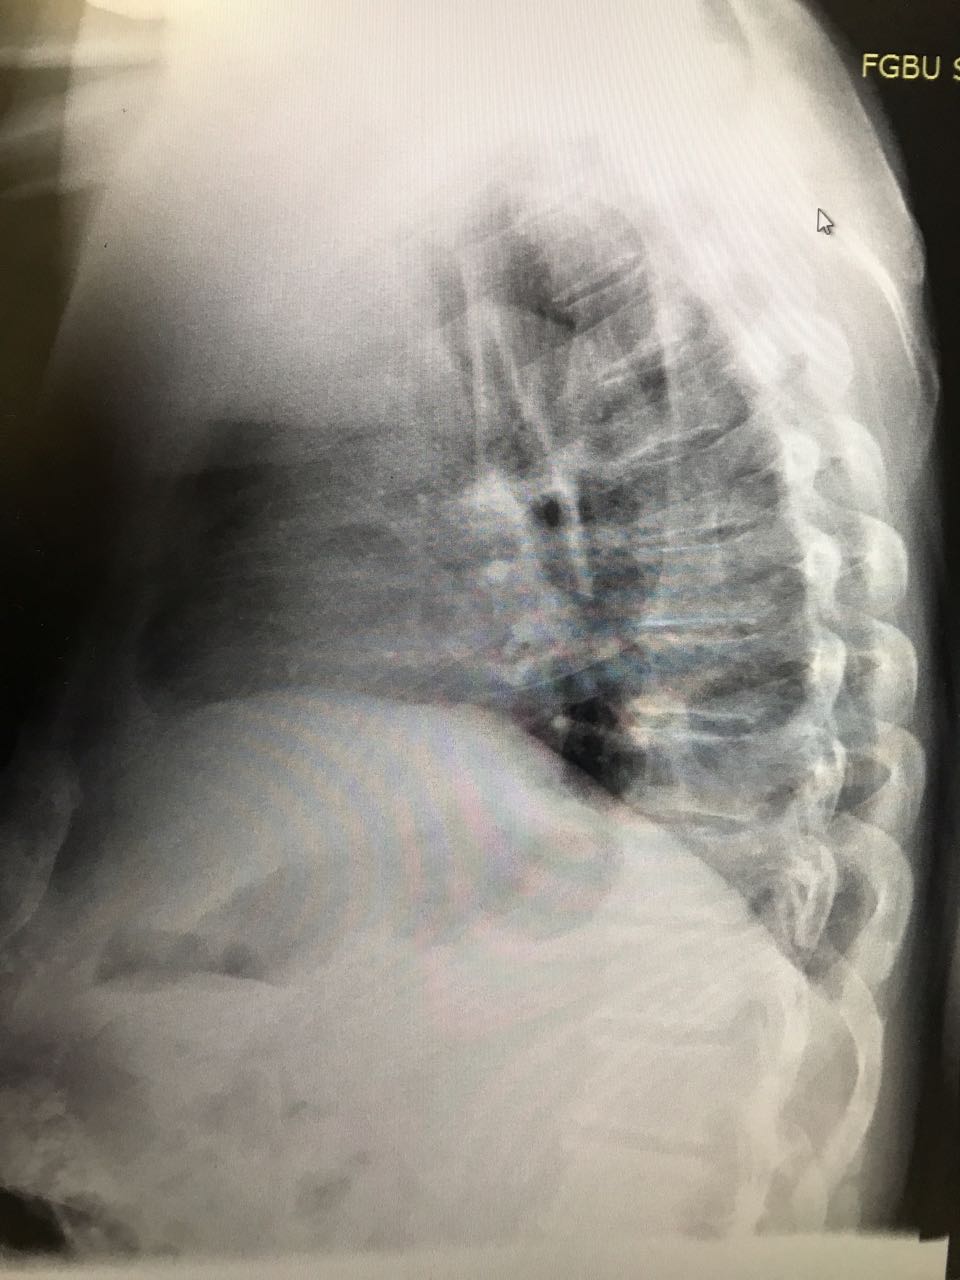

На рентгене гиповентиляция - признак центрального рака

Обсуждалось в Госпитале Ослабленных Сердец

Вложения:

1.jpg

1.jpg [ 153.7 KiB | Просмотров: 59333 ]

2.jpg

2.jpg [ 116.83 KiB | Просмотров: 59333 ]

IMG_7902-.jpg

IMG_7902-.jpg [ 380.61 KiB | Просмотров: 59333 ]

Rotation of IMG_7904-.jpg

Rotation of IMG_7904-.jpg [ 467.04 KiB | Просмотров: 59333 ]